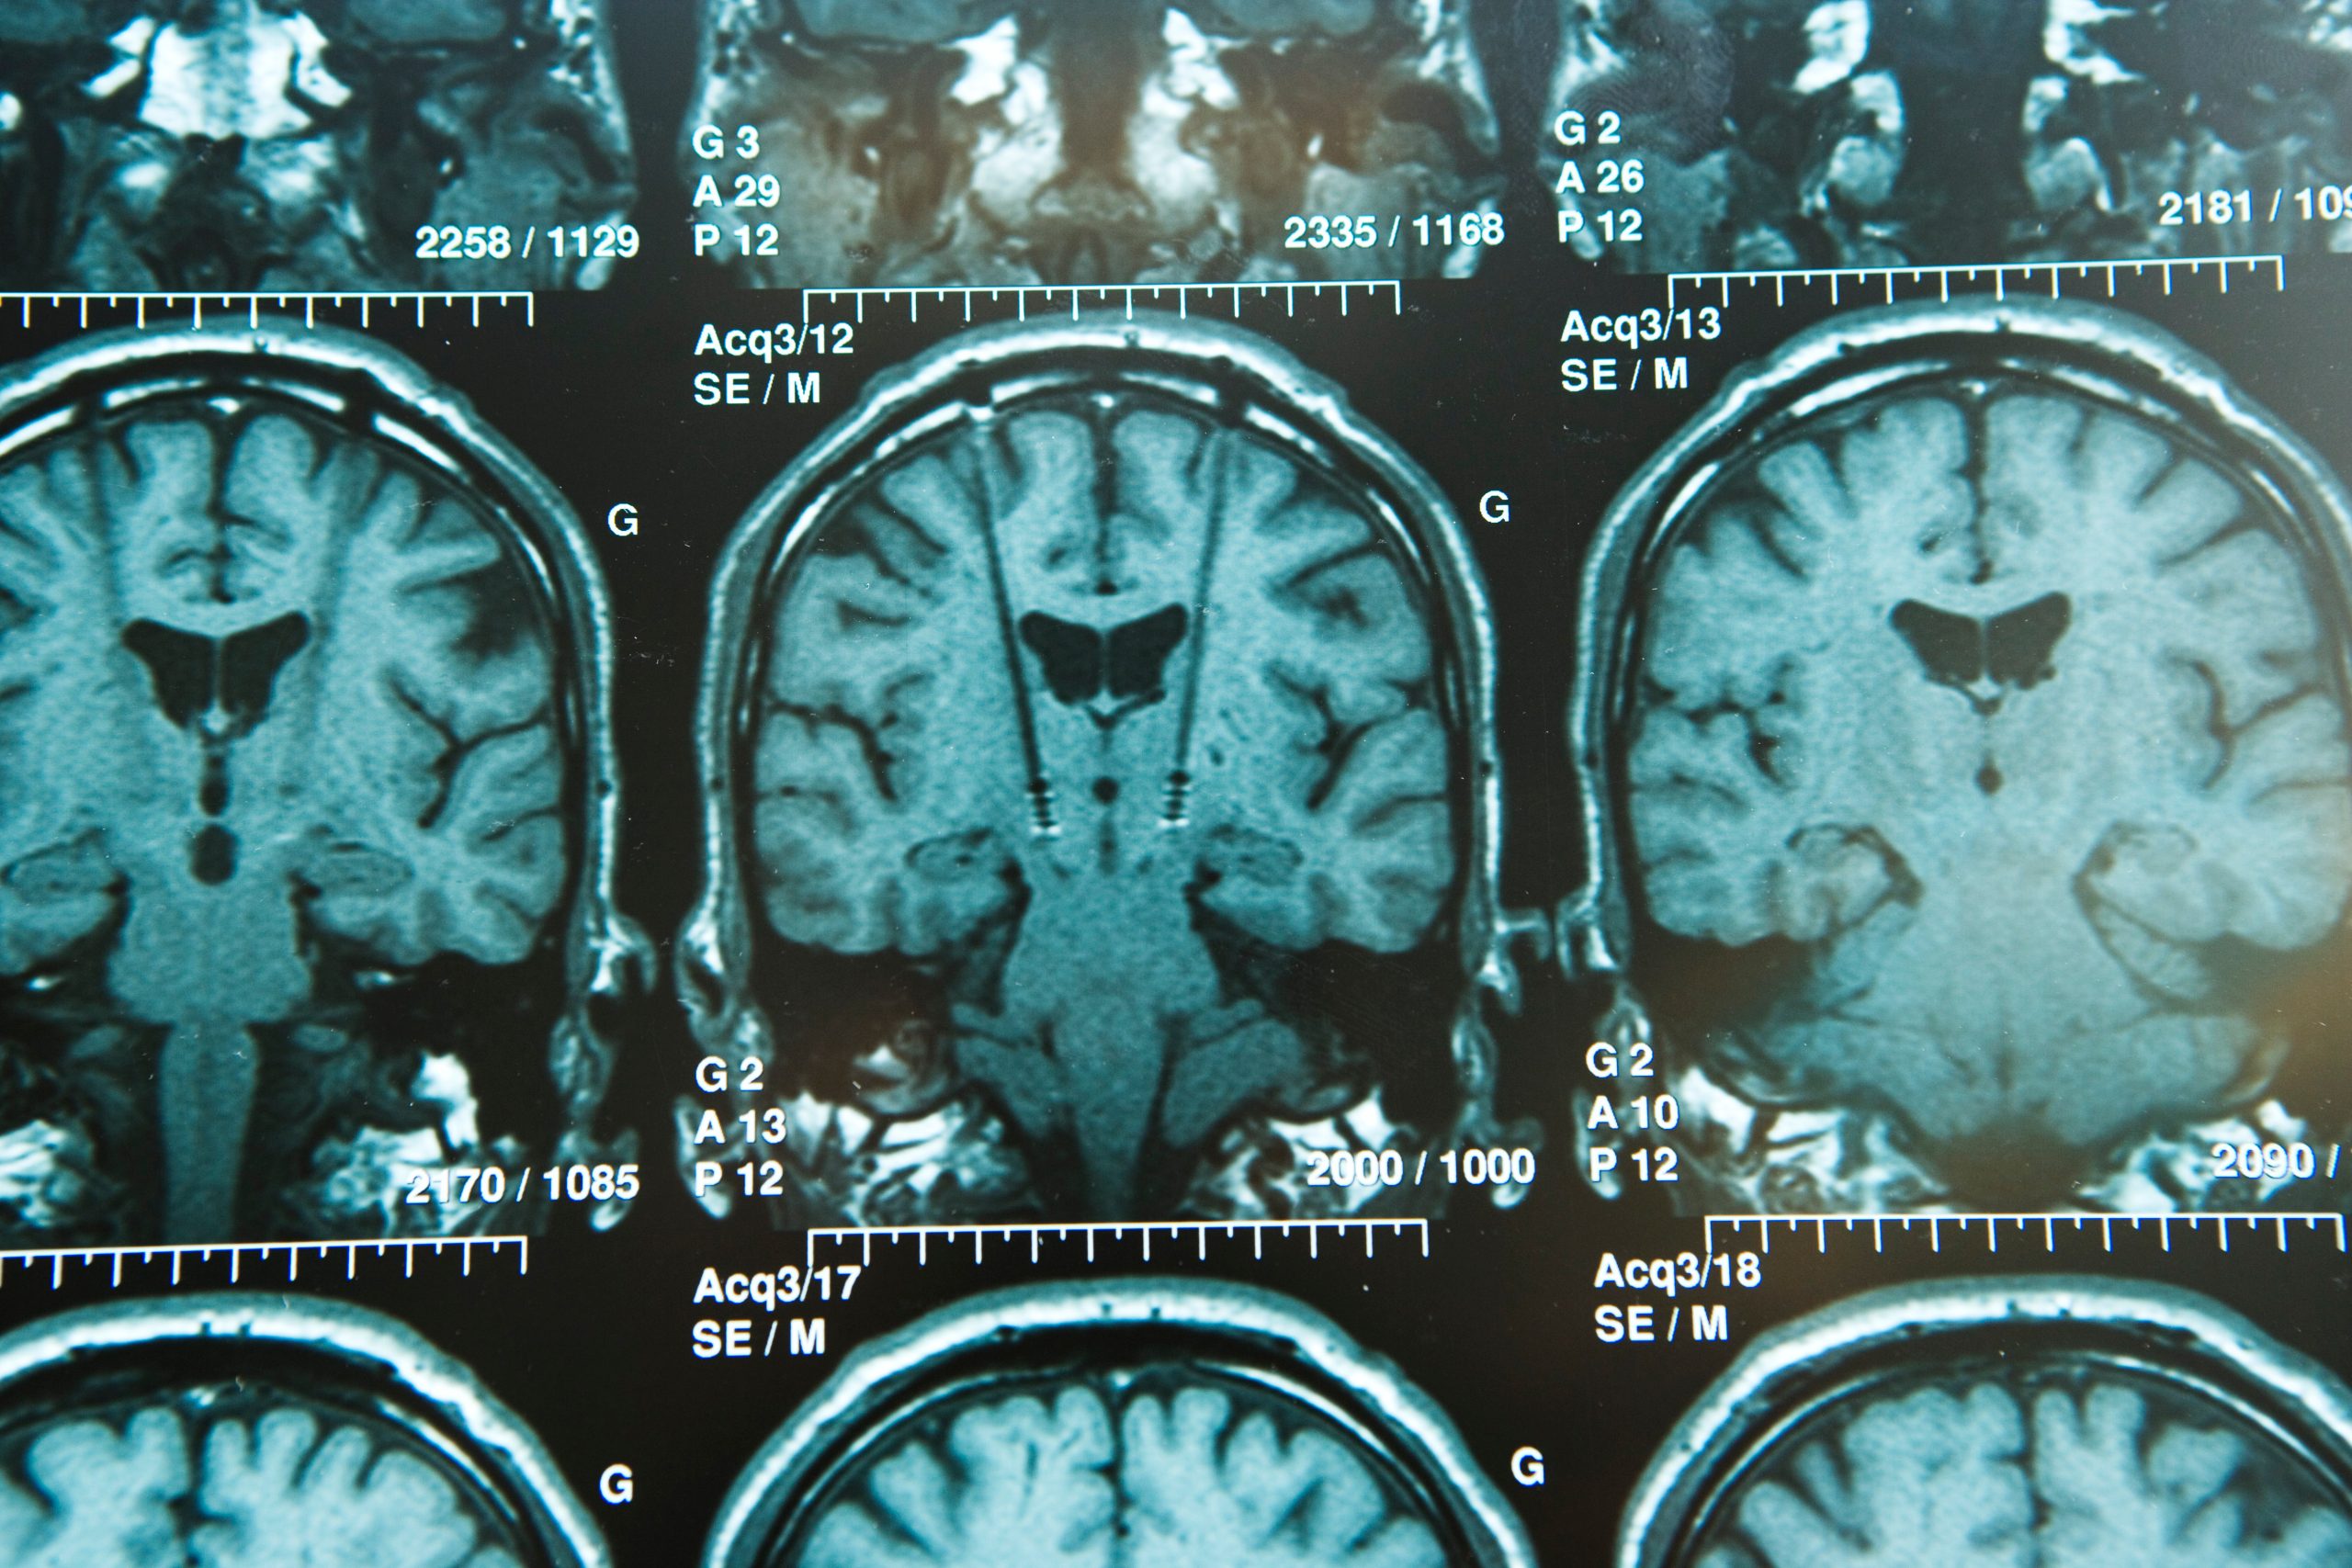

Restoring mobility through neurostimulator implants that help paralyzed patients walk again